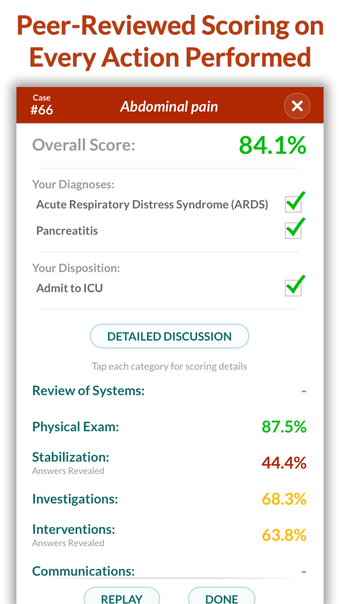

Full Code - Emergency Medicine Simulation è un'applicazione Android sviluppata da Minerva Medical Simulation Inc. È una versione completa con licenza di un'applicazione di stile di vita che rientra nella sottocategoria medica. È un'applicazione di simulazione intuitiva, mobile-first che offre oltre 160 casi virtuali realistici e un'interfaccia coinvolgente simile a un gioco, preferita dai professionisti medici di tutto il mondo. L'applicazione è progettata per aiutare gli studenti e i professionisti medici a acquisire fiducia nel trattamento di casi complessi e offre 0,5 crediti AMA PRA Categoria 1™ per ogni caso Full Code giocato con Full Code Pro+CME.

L'applicazione consente agli utenti di esercitarsi in diagnosi cliniche rare e rischiose in un ambiente sicuro in modo da poter affrontare casi complessi del mondo reale con fiducia. Con oltre 160 casi in 31 specialità, Full Code consente di esercitarsi in simulazioni mediche on-demand ogni volta che si ha una pausa, ovunque ci si trovi. L'applicazione è ottimizzata per la portabilità e l'accessibilità ed è disponibile su qualsiasi dispositivo mobile, desktop o tablet. Full Code è accreditato attraverso l'ACCME e, con la sua sottoscrizione PRO+CME, gli utenti possono completare i loro requisiti di formazione medica continua (CME) con sfide di simulazione flessibili e piacevoli. È un'applicazione eccellente per i professionisti medici che vogliono migliorare le proprie competenze e acquisire fiducia nel gestire casi complessi.